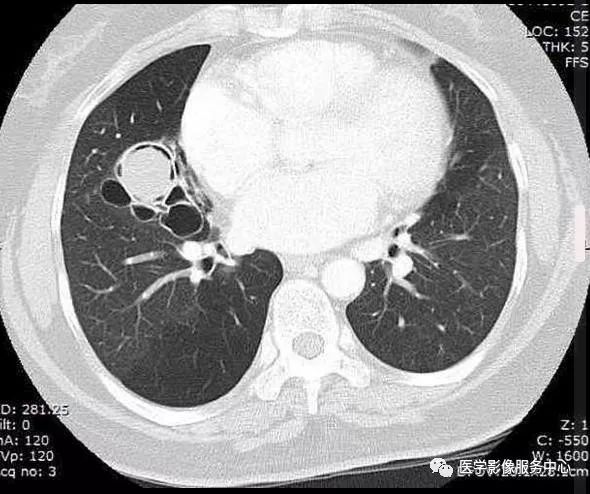

病史:患者女性,慢性咳嗽就诊

胸片正侧位:右肺中叶见一圆形边界清楚的高密度结节影。 病变中似有“空气新月征”。

CT:右肺中叶见一个球形软组织密度影,周围见空气新月征

(1)致密阴影在空洞内随体位的改变而移动。在直立的胸部x线片,空气新月征位于致密阴影上;然而,在患者仰卧的CT图像上,空气新月征位于致密阴影前。

该患者右肺中叶切除术后,病理:肺曲菌球

讨论:曲菌球,常继发于支气管囊肿、支气管扩张、肺脓肿和肺结核空洞。是曲霉在慢性肺部疾病原有的空腔内繁殖、蓄积,与纤维蛋白、粘液及细胞碎屑凝聚成曲霉肿。可发生任何年龄,痰中带血或咯血为主要临床特点,其他临床症状无特异性。

CT:初为肺部局限性炎症,表现为斑片状模糊阴影,继发周围炎症吸收,表现为团块状或结节状阴影,周围环以浅淡的磨玻璃样的晕,当肺组织液化,坏死物咳出后,则表现为:新月状的空气所包绕的一致密阴影,该致密阴影边缘光整,密度较均匀,增强无强化,且致密阴影在空洞内随体位的改变而移动。

结论:工作中虽然少见,但影像诊断上有特异性,主要与肺肿瘤、肺结核、肺脓肿等鉴别,关键看病变是否随体位改变而移动,临床上,此病多见于免疫功能低下和长期应用抗菌素、激素的病人以及糖尿病患者。